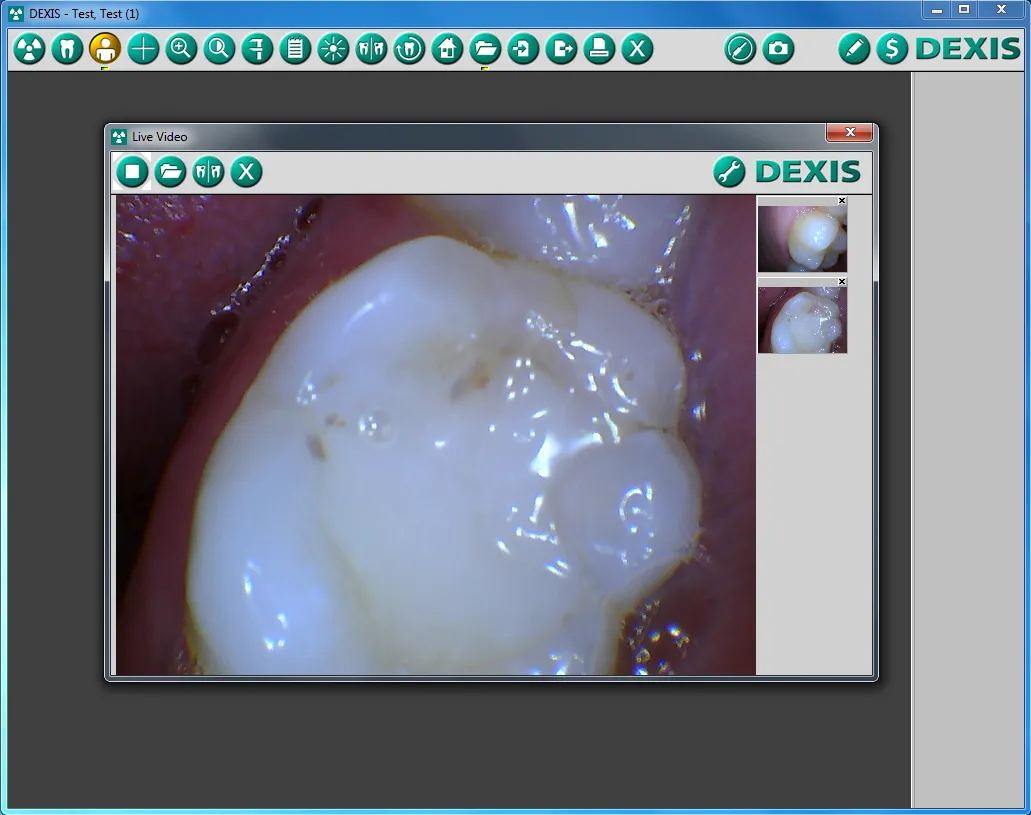

When examining your teeth and mouth, our dentist and team may use an intraoral camera. Intraoral cameras are small, pen-shaped devices used to take high-quality color photos of your teeth and gums. They are easily maneuverable and can be used to view all areas of your mouth, including the areas that are otherwise impossible for our dentist to reach. This imaging technology is also comfortable and noninvasive, and the camera can be removed quickly from your mouth as needed.

Intraoral cameras are also one of the most useful educational tools our dentist and team use. The images captured by the camera can be displayed almost instantly on a nearby monitor, allowing you to see for yourself what is happening in your mouth and better understand your oral health and treatment options. Additionally, the photos can be sent to other dentists, specialists and insurance companies as needed.